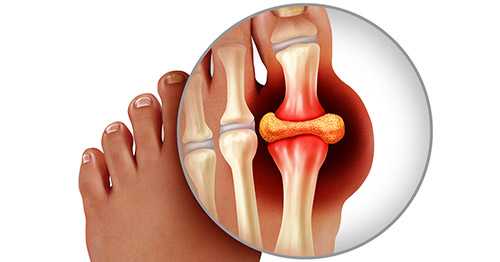

С греческого языка подагра переводится как «нога в капкане», так как заболевшего преимущественно беспокоит интенсивная боль в первом плюснефаланговом суставе стопы, колене или голеностопе. Также возможно вовлечение кисти по типу олиго или полиартрита (воспаление двух или многих суставов). При этом сустав становится отечным, кожа над ним приобретает красный оттенок, начинает лосниться. Такая форма заболевания называется острым подагрическим артритом.

При переходе в хроническую форму подагрический артрит сопровождается деформацией и ограничением движений в суставах, боль разной интенсивности приобретает постоянный характер. В дальнейшем отложения кристаллов мочевой кислоты становятся видимыми. Под кожей, чаще в области суставов, появляются тофусы - узелки белого или желтого цвета с крошковидным, творожистым содержимым. Над ними возможно образование язв, гнойных ран.

Изменения в суставах

В результате повышенного содержания мочевой кислоты в организме происходит отложение уратов в области суставов. Болевой синдром возникает в результате проникновения кристаллов мочевой кислоты внутрь и выработки веществ, провоцирующих воспаление.

Подагрическая атака - результат раздражающего действия кристаллов. Вырабатываемые в ответ на воспаление иммунные клетки начинают разрушать суставную структуру.